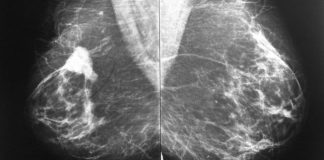

¡Ese dolor repentino que nos obliga a quitarnos los zapatos!

La enfermedad de Morton es una inflamación neurálgica que afecta el nervio sensorial interdigital del pie. En general, el paciente que sufre de esta...